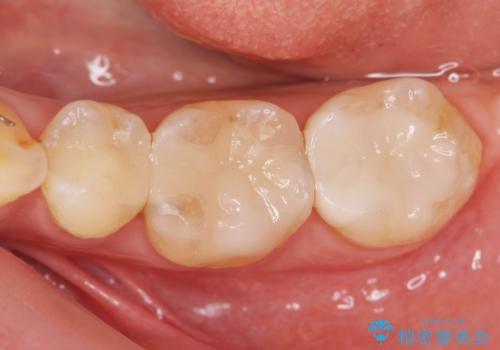

歯槽堤保存を併用し清掃性を高めたブリッジ治療

担当医 大元洋佑